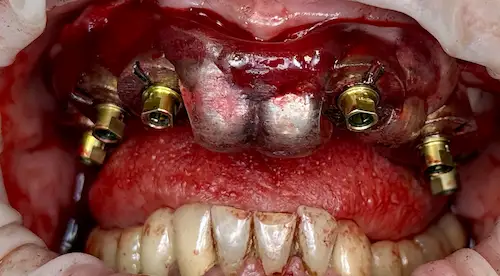

All-on-4 ® – Patientenfall

Bei Zahnlosigkeit oder nicht mehr erhaltungswürdigen Zähnen wünschen sich die Patient*innen der Praxisklinik Herne natürlich zeitnahe und minimalinvasive Lösungen. Dank des All-on-4 ® / All-on-6 ®–Konzepte können wir ihnen diesen Wunsch oftmals innerhalb nur eines einzigen Behandlungstages erfüllen: 4 bzw. 6 Zahnimplantate werden gesetzt und bilden im Folgenden die Grundlage für den passenden festsitzenden oder herausnehmbaren Zahnersatz. Die einzelnen Behandlungsschritte veranschaulichen wir Ihnen anhand eines aktuellen Patientenfalls aus diesem Jahr.

Der Patientenfall

Unser 55-jähriger Patient stellte sich uns nach Jahrzehnten der Nichtbehandlung mit einen stark kariösen und nur zum Teil bezahnten Kiefer vor. Aufgrund einiger abgebrochener Zahnwurzeln wurde schnell ersichtlich: Der bisherige Zahnersatz kann nicht erneuert werden; außerdem wünschte sich unser Patient in Zukunft einen gaumenfreien festsitzenden Zahnersatz. Alles deutete Richtung All-on-4 ® / All-on-6 ®–Konzept.

Der chirurgische Eingriff im Detail

Der Tag der Operation ist gekommen: Im ersten Schritt werden die noch vorhandenen Zähne gezogen sowie die Wurzeln und vereinzelte Zysten restlos entfernt. Dies erwies sich im vorliegenden Fall als extrem komplex und folgenreich: Beim Extrahieren gingen Teile der Knochenwände verloren, was einen deutlichen Mehraufwand beim Aufbau des Kieferkamms nach sich zog. Zuzüglich zu Knochenersatzmaterial verwendete Dr. Mintert dafür 2 Collagen Blöcke, 2 Membranen und 0,3 ml Emdogain. Letzteres dient der Entwicklung von zahnstützendem Gewebe. Auch Eigenknochen aus einem zweiten OP-Gebiet kam zum Einsatz. Im Oberkiefer wurde außerdem ein sogenannter Sinuslift durchgeführt, der – vereinfacht gesprochen – die Kieferhöhlen anheben soll. Nun waren die Grundlagen für den nächsten Schritt geschaffen: Eine eigens angefertigte Bohrschablone ermöglicht die navigierte Implantation. So fanden alle acht Implantate trotz ungeplanter Komplikationen ihren rechten Platz im Mundraum. Abschließend wird L-PRF Plasma, d.h. zentrifugiertes Eigenblut eingebracht, um die Wundheilung zu unterstützen. Als Zahnersatz werden zwei festsitzende Keramikbrücken gewählt und auf künstliche Keramikaufbauten geklebt. Diese wiederum sind mit jeweils vier Implantaten verschraubt.